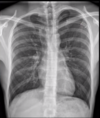

RN a termo.

Cardiomegalia massiva em um neonato com pulmão normal (sem edema alveolar ou intersticial, sem derrame pleural)

Cardiomiopatia neonatal.